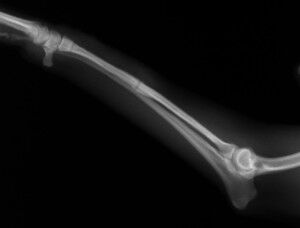

こんばんは、フジタどうぶつ病院です。今日はトイ・プードルの橈尺骨骨折の治療についてご報告させて頂きます。トイ・プードルは脚が長く、骨が細いので非常に骨折が多い犬種です。椅子やソファーから降りた時に折れたり、中には飼い主さんの後ろを歩いていて気づいたら脚を挙げていて病院でレントゲンを撮ったら折れていた、ということもあるようです。今回の症例報告のワンちゃんは椅子から降りた時に折れてしまったようです。下の写真が病院に来院時に撮ったレントゲン写真です。前脚の橈骨と尺骨が折れています。